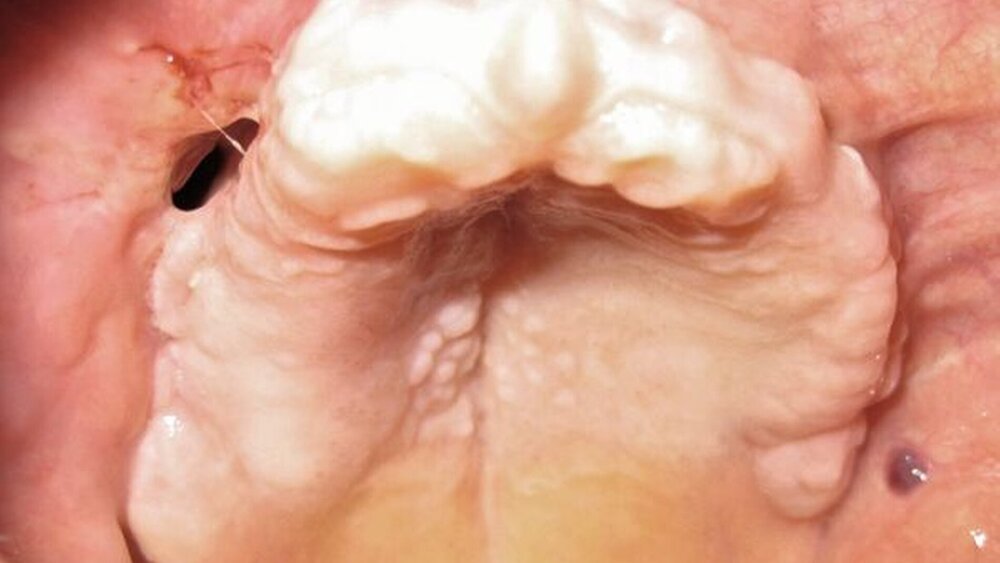

Als therapeutische Maßnahme erfolgte zunächst unter Intubationsnarkose die Extraktion aller Zähne im Oberkiefer. Hierbei konnte ein großflächiges Knochensequester aus dem ersten Quadranten in toto geborgen werden. Die rechte Kieferhöhle erschien dadurch breitflächig eröffnet, es erfolgte eine ausgiebige Ausräumung des Granulationsgewebes und die Einlage einer Furacintamponade mit Ausleitung zum unteren Nasengang. Der noch verbleibende Alveolarfortsatz des Oberkiefers wurde großflächig dekortiziert, bis sich eine Blutung aus dem Knochen zeigte. Die Deckung erfolgte dann lokal mit Mukoperiostlappen.